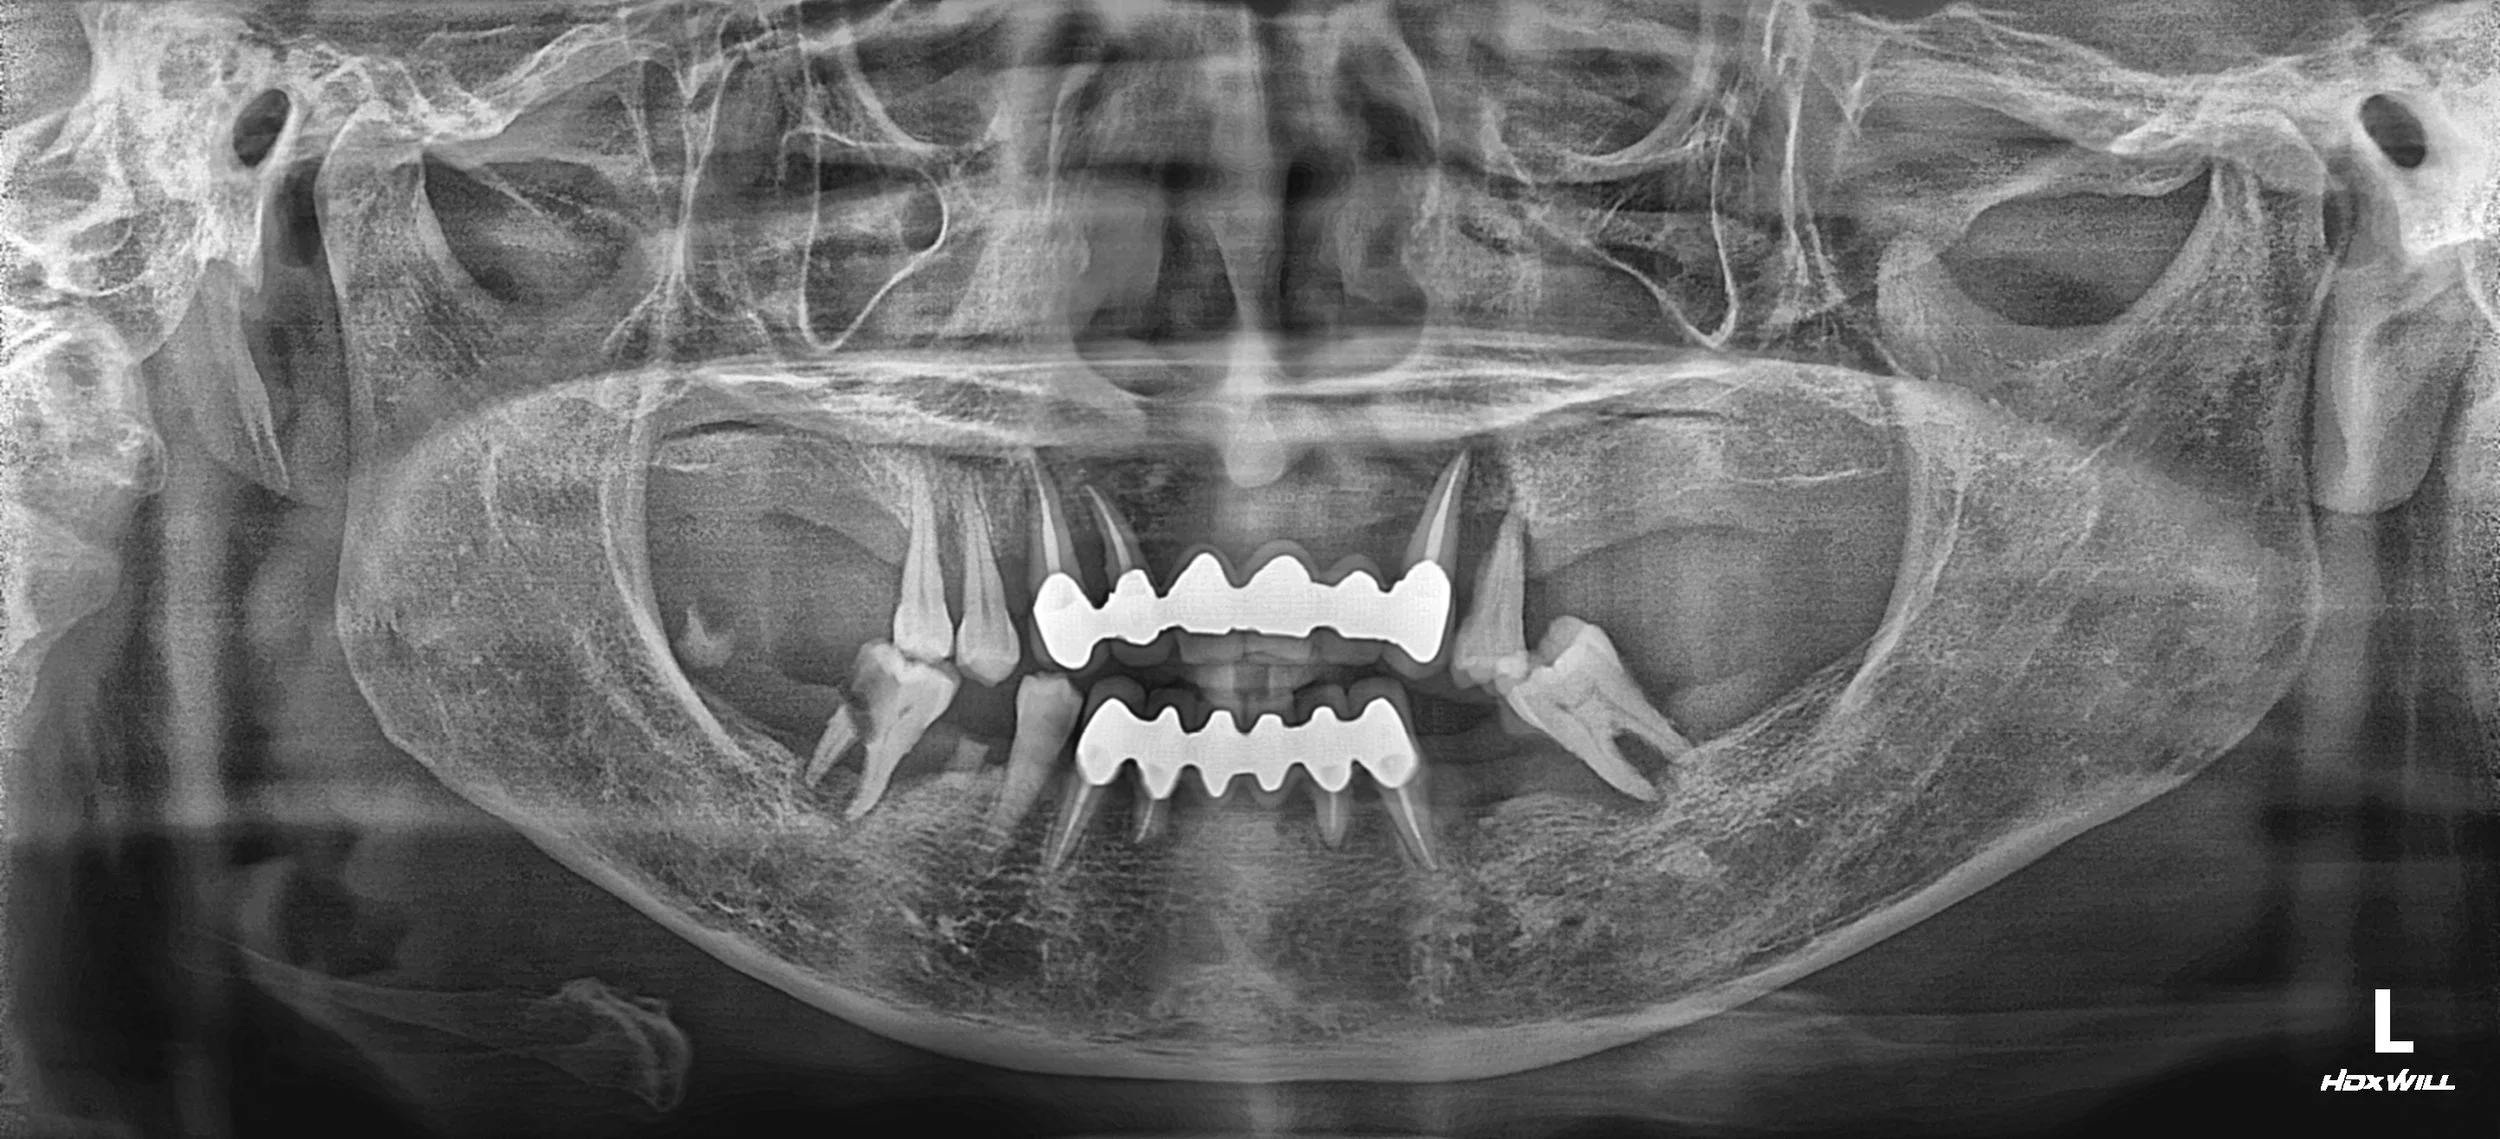

Contact

35. Comprehensive Full-Arch Transformation: Restoring Confidence in a Young Phobic Patient

Reversing the effects of generalized rampant caries and occlusal collapse in a female patient in her 20s. A tooth-preserving, implant-assisted approach focused on stable VDO elevation and overcoming social anxiety.